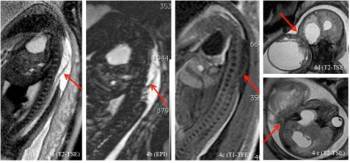

Základní metodou screeningu rozštěpových vad neurální trubice je v těhotenství klasické dvojrozměrné ultrazvukové vyšetření (obrázek č. 2 a 3). Upřesnit diagnostiku může umožnit trojrozměrný ultrazvuk (obrázek č. 3) a magnetická rezonance (obrázek č. 4).

Obrázek č. 4.: Vyšetření magnetickou rezonancí u plodu s rozsáhlým otevřeným rozštěpem páteře (spina bifida aperta- meningomyelokéla) (obrázek č. 4a–4c) a s rozsáhlou ecefalo-meningokélou (4d a 4e). Šipky směřují k defektu.

(Foto: MUDr. Veronika Frisová, Profema)